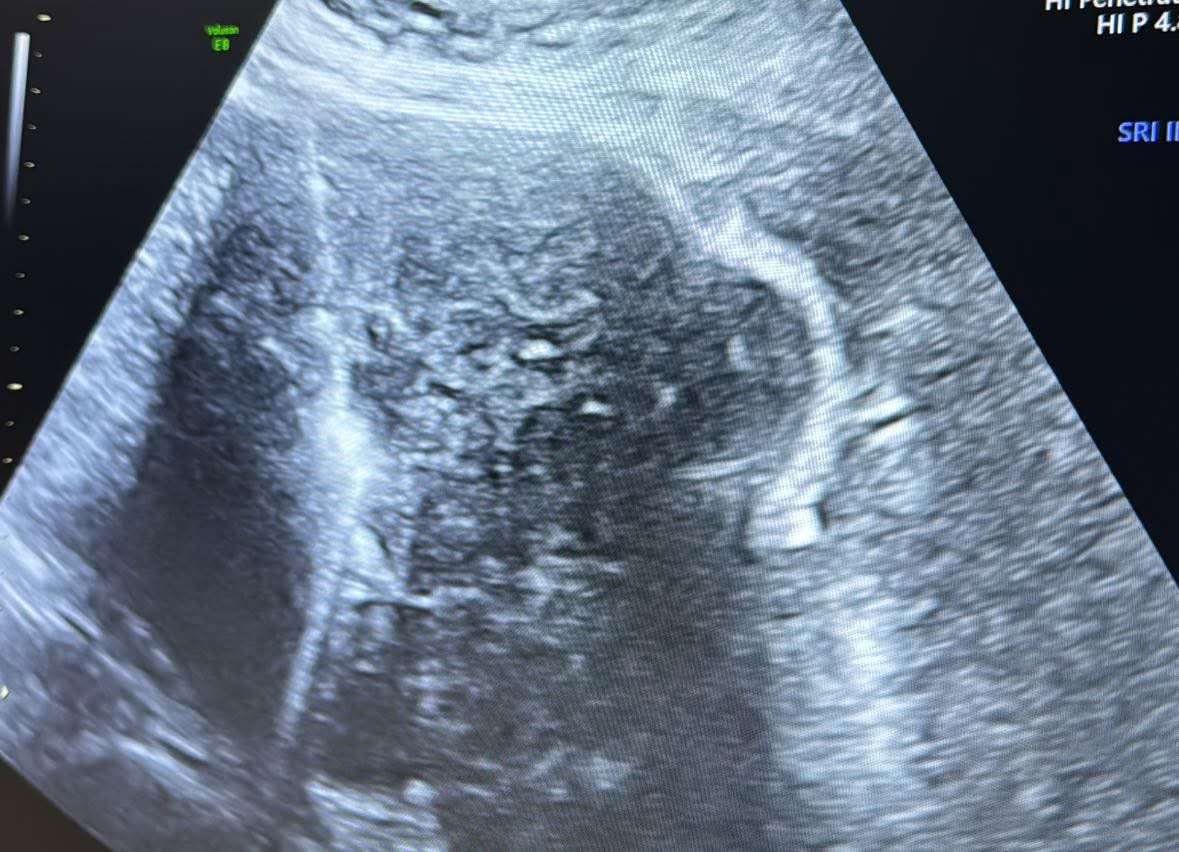

A major focus was on microwave ablation techniques for uterine fibroids and adenomyosis, led by our Course Director, Dr. Gong Xiaoming. The event featured 5 live surgeries, including percutaneous microwave ablation, transvaginal ablation, laparoscopic ablation, and live endometrial ablation demonstration, along with model drills and lectures. Dr. Gong shared key insights on patient selection, imaging, and complications, fostering valuable international dialogue.